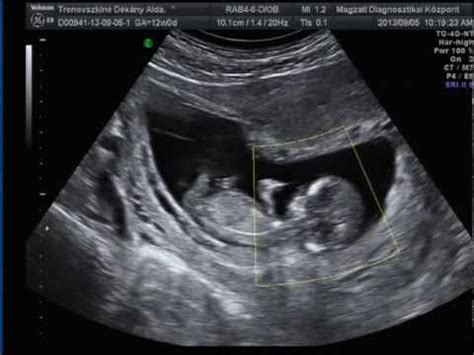

A 12. hét az első fontos mérföldkő a kismamák életében, mert a legmeghatározóbb vizsgálatra, a kromoszóma rendellenesség szűrésére ekkor kerül sor. A 12 hetes genetikai ultrahang vizsgálat a terhesség 11-13. hete között történik. A vizsgálatról a legtöbb helyen már felvétel is készül, amit a szülők megkaphatnak.

A terhesség alatt rendszeres orvosi és védőnői vizsgálatokra van szükség. Az első genetikai ultrahang a 11-13. hét között történik. A 18. héten a második genetikai ultrahang vizsgálat következik. A 24-28. terhességi hét között vérvételre, terhességi vizeletvizsgálatra, és terheléses vércukor vizsgálatra kerül sor.

- 12. hét: Az agy szerkezete megegyezik a születendő agyéval. Megindult az epekiválasztás.